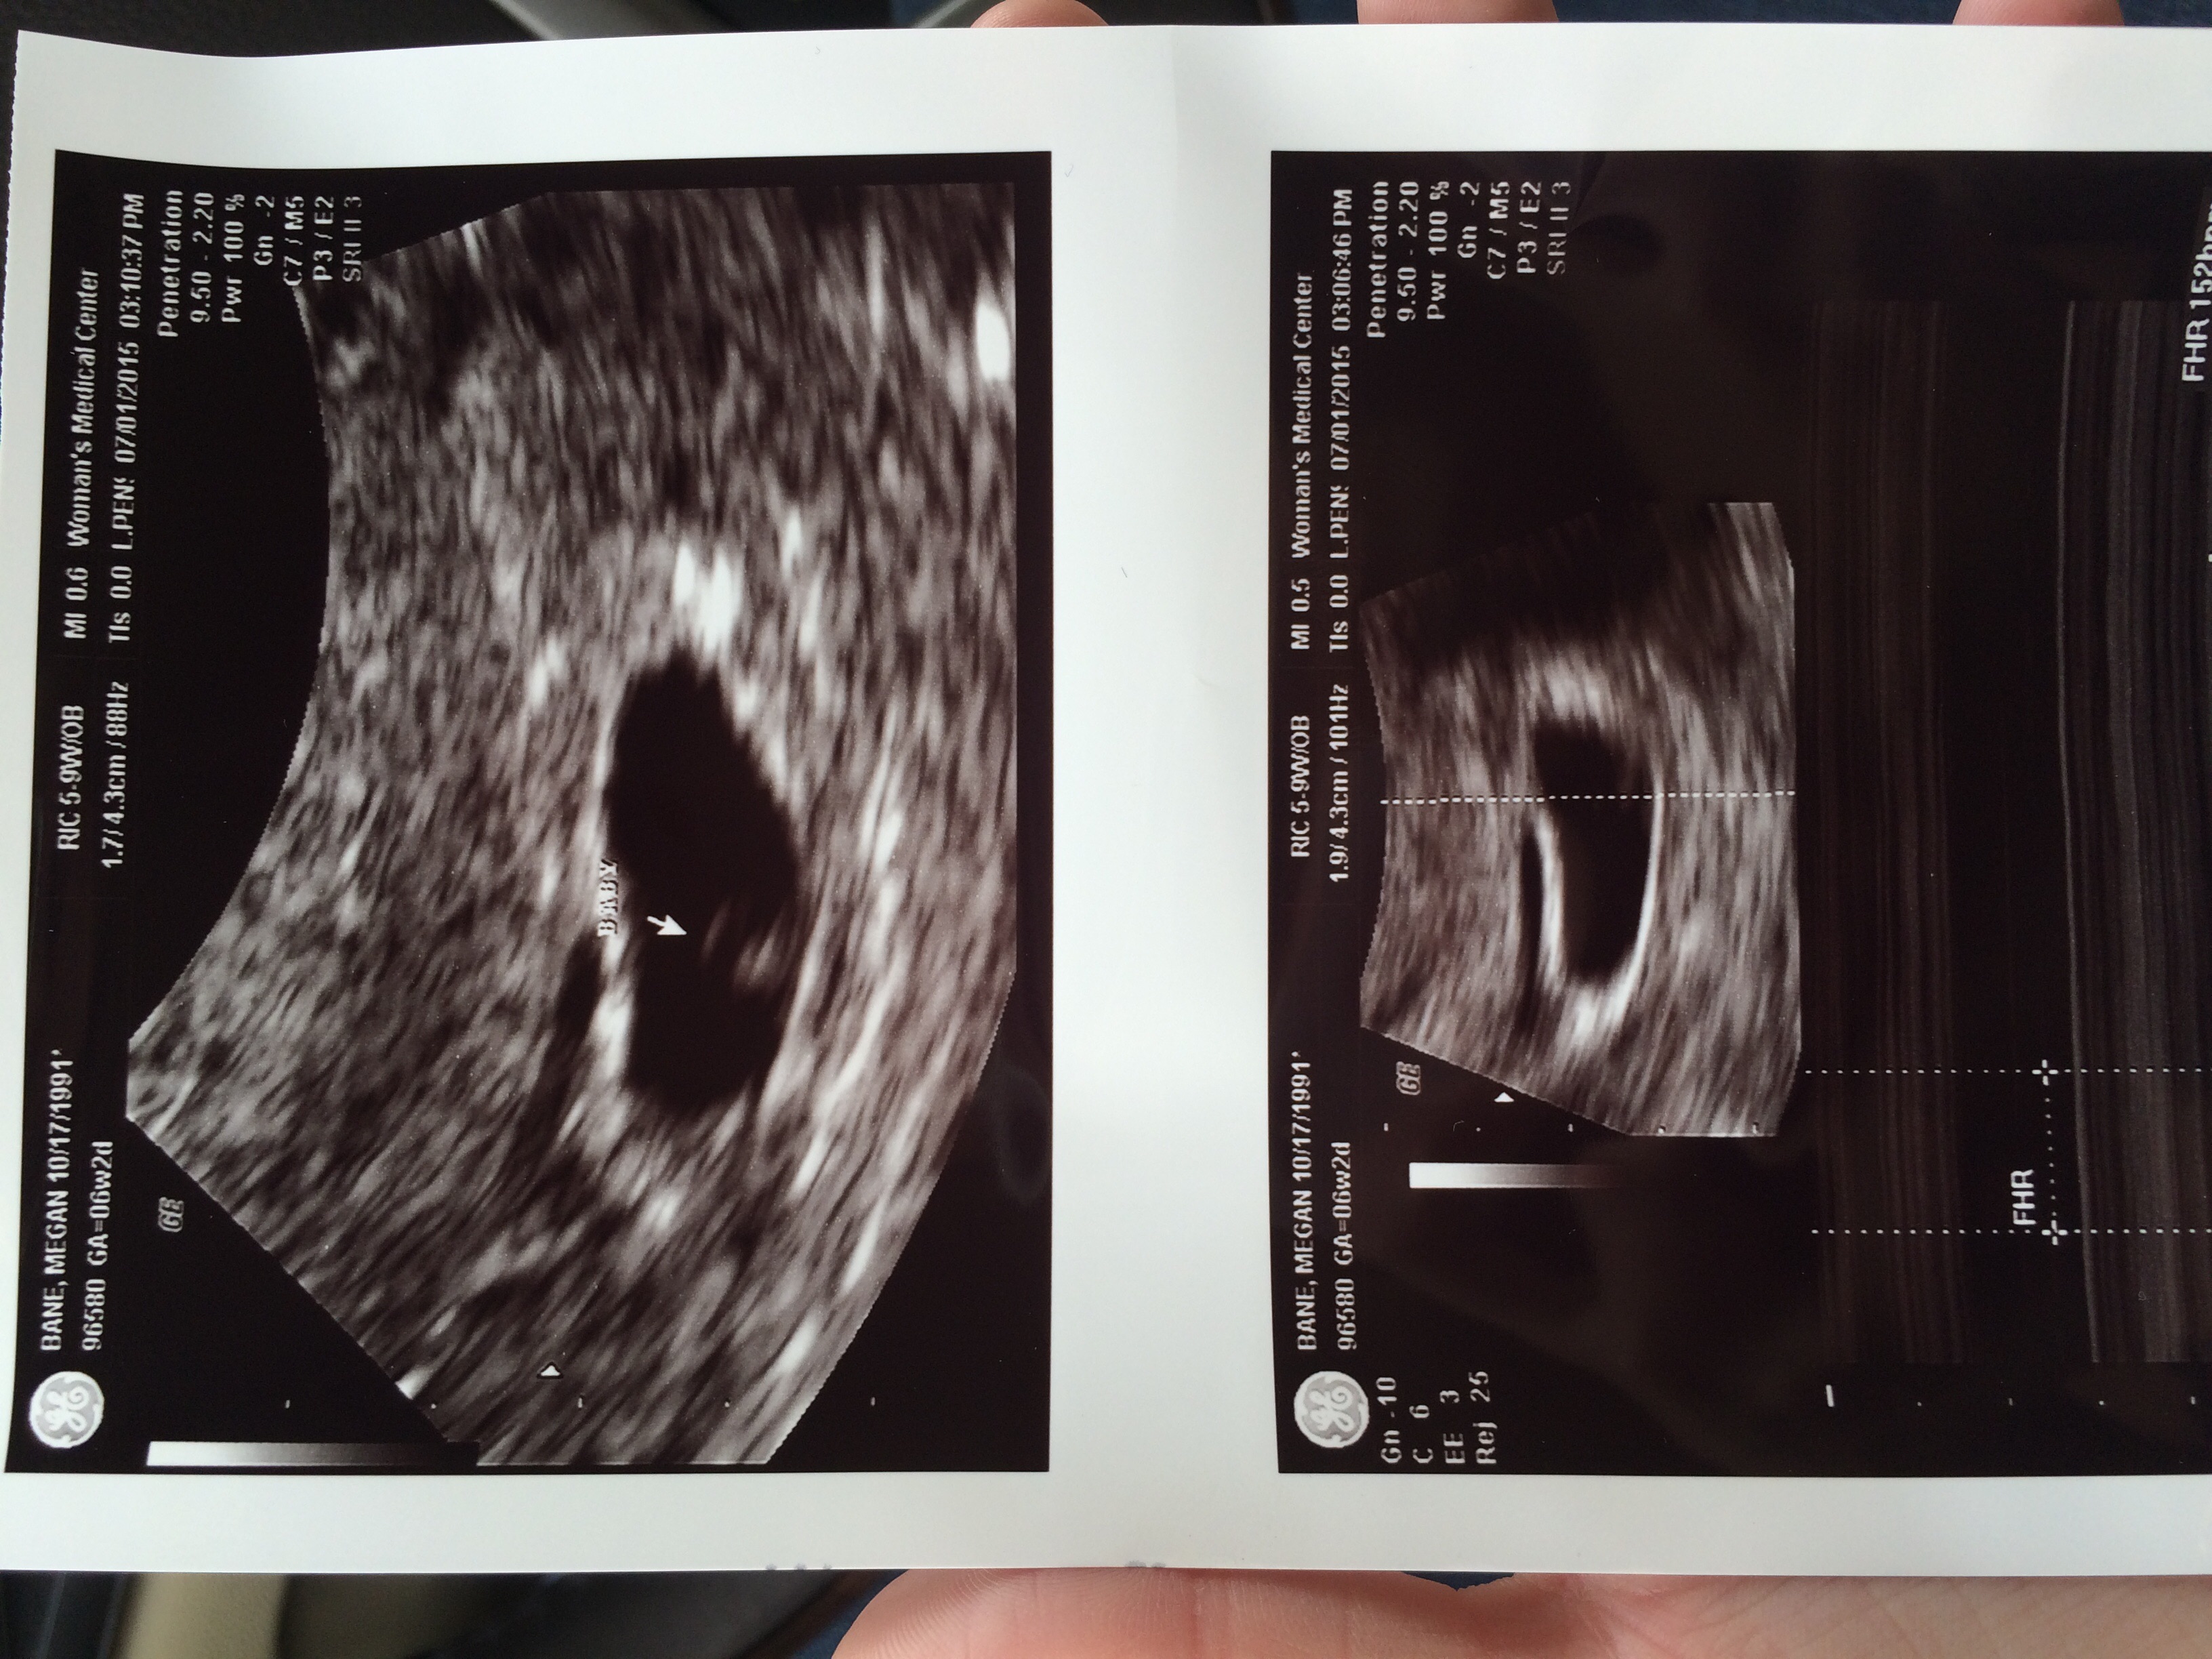

• Our sweet bean :) at 8 weeks 5 days

• @martin91 make sure you crop your photo because it's got some of your personal information on the top

This is my first post, but I am due 2/5/16 with my first little one. Heart rate was 167, and I'm 9w2d right now. US was taken at 8w4d